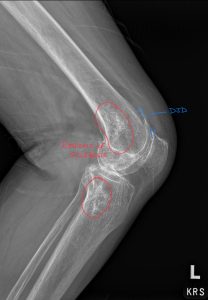

Fig. 3 Annotated xray of the knee shows regions of sclerosis (outlined in red) involving the distal femur, proximal tibia, and fibular head.